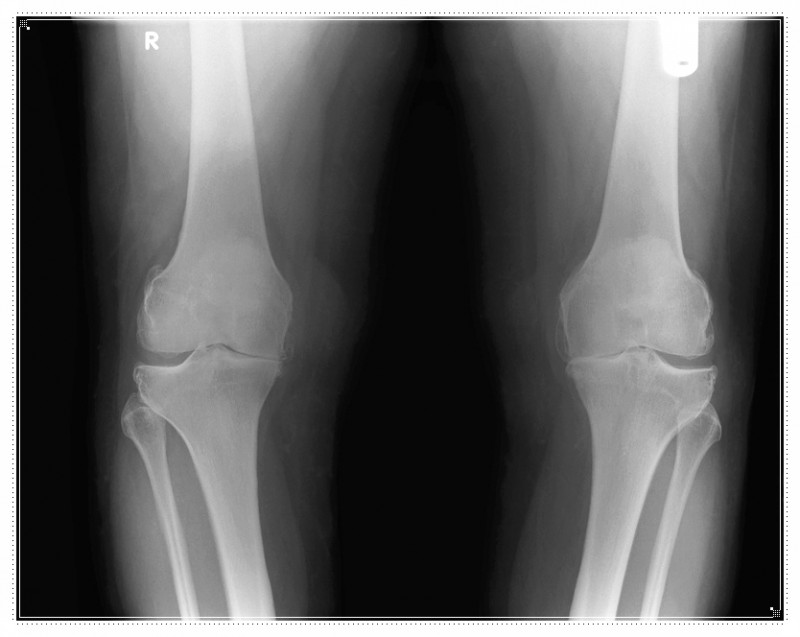

![]()